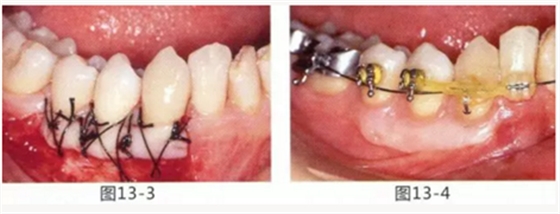

由于口腔前庭較淺且沒有附著齦,使菌斑容易滯留且刷牙困難的病例

圖13-1 使用碘溶液進行染色,頰側基本看不到角化牙齦,且無口腔前庭的狀態(tài)。

圖13-2 為了擴張口腔前庭,獲取附著齦而進行了游離齦移植術。受皮床一定不能發(fā)生移動,盡可能使厚度均等。

圖13-3 手術剛結束的狀態(tài)。通過骨膜縫合的褥式縫合將移植片固定,使其無法移動。

圖13-4 手術完成2年后的狀態(tài)。口腔前庭得到擴張,即使正在進行正畸治療,也沒有妨礙到清潔。